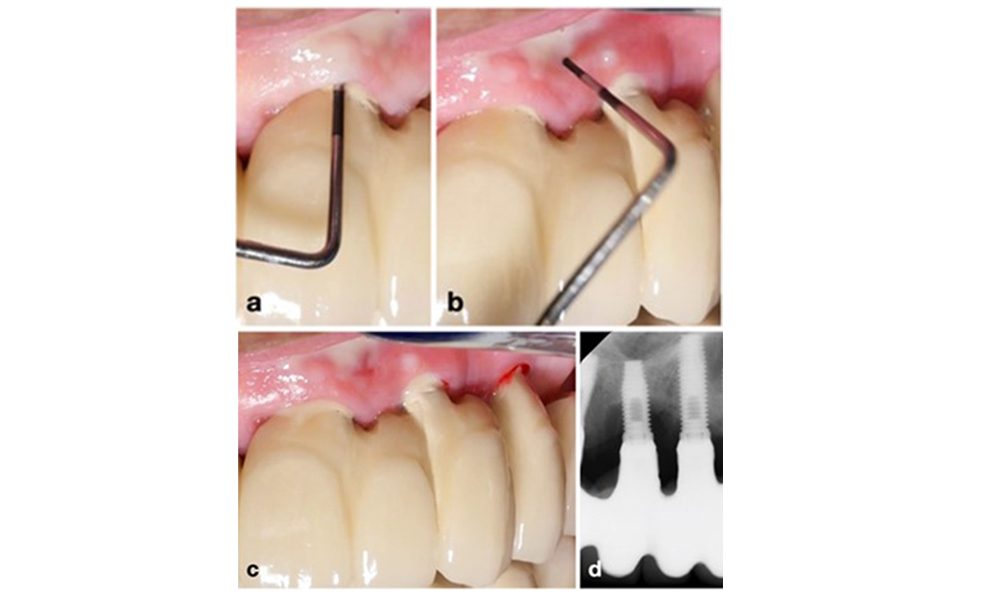

Pour obtenir des radiographies cohérentes et comparables dans le temps sans chevauchement des fils d'implant, une règle mnémotechnique simple peut être suivie : "flou à droite, faisceau plus haut & flou à gauche, faisceau plus bas - RBRB/LBLB" (voir figure 3 adaptée de Schropp et al. 2012).

Pour obtenir des radiographies intra-orales optimales des implants dentaires, suivez cette règle mnémotechnique : si le côté droit de l'implant apparaît flou sur la radiographie péri-apicale, élevez le faisceau (c'est-à-dire dirigez-le davantage vers le plafond) (a) ; si le côté gauche apparaît flou, abaissez le faisceau (c'est-à-dire dirigez-le davantage vers le sol) (b). Cette règle s'applique quelle que soit la position de l'implant dans la mâchoire supérieure ou inférieure. Exemple : Des filets flous sur les implants en positions 14 et 16, principalement sur leur côté droit, (c) ont été corrigés en élevant le faisceau d'environ 15 degrés, ce qui a permis d'obtenir une image claire montrant le contact entre l'os et l'implant (d).

Figure 3. Pour des radiographies intra-orales optimales des implants dentaires, suivez cette règle mnémotechnique : si le côté droit de l'implant apparaît flou sur la radiographie péri-apicale, élevez le faisceau (c'est-à-dire orienté davantage vers le plafond) (a) ; si le côté gauche apparaît flou, abaissez le faisceau (c'est-à-dire orienté davantage vers le sol) (b). Cette règle s'applique quelle que soit la position de l'implant dans la mâchoire supérieure ou inférieure. Exemple : Des filets flous sur les implants en positions 14 et 16, principalement sur leur côté droit, (c) ont été corrigés en élevant le faisceau d'environ 15 degrés, ce qui a permis d'obtenir une image claire montrant le contact entre l'os et l'implant (d).